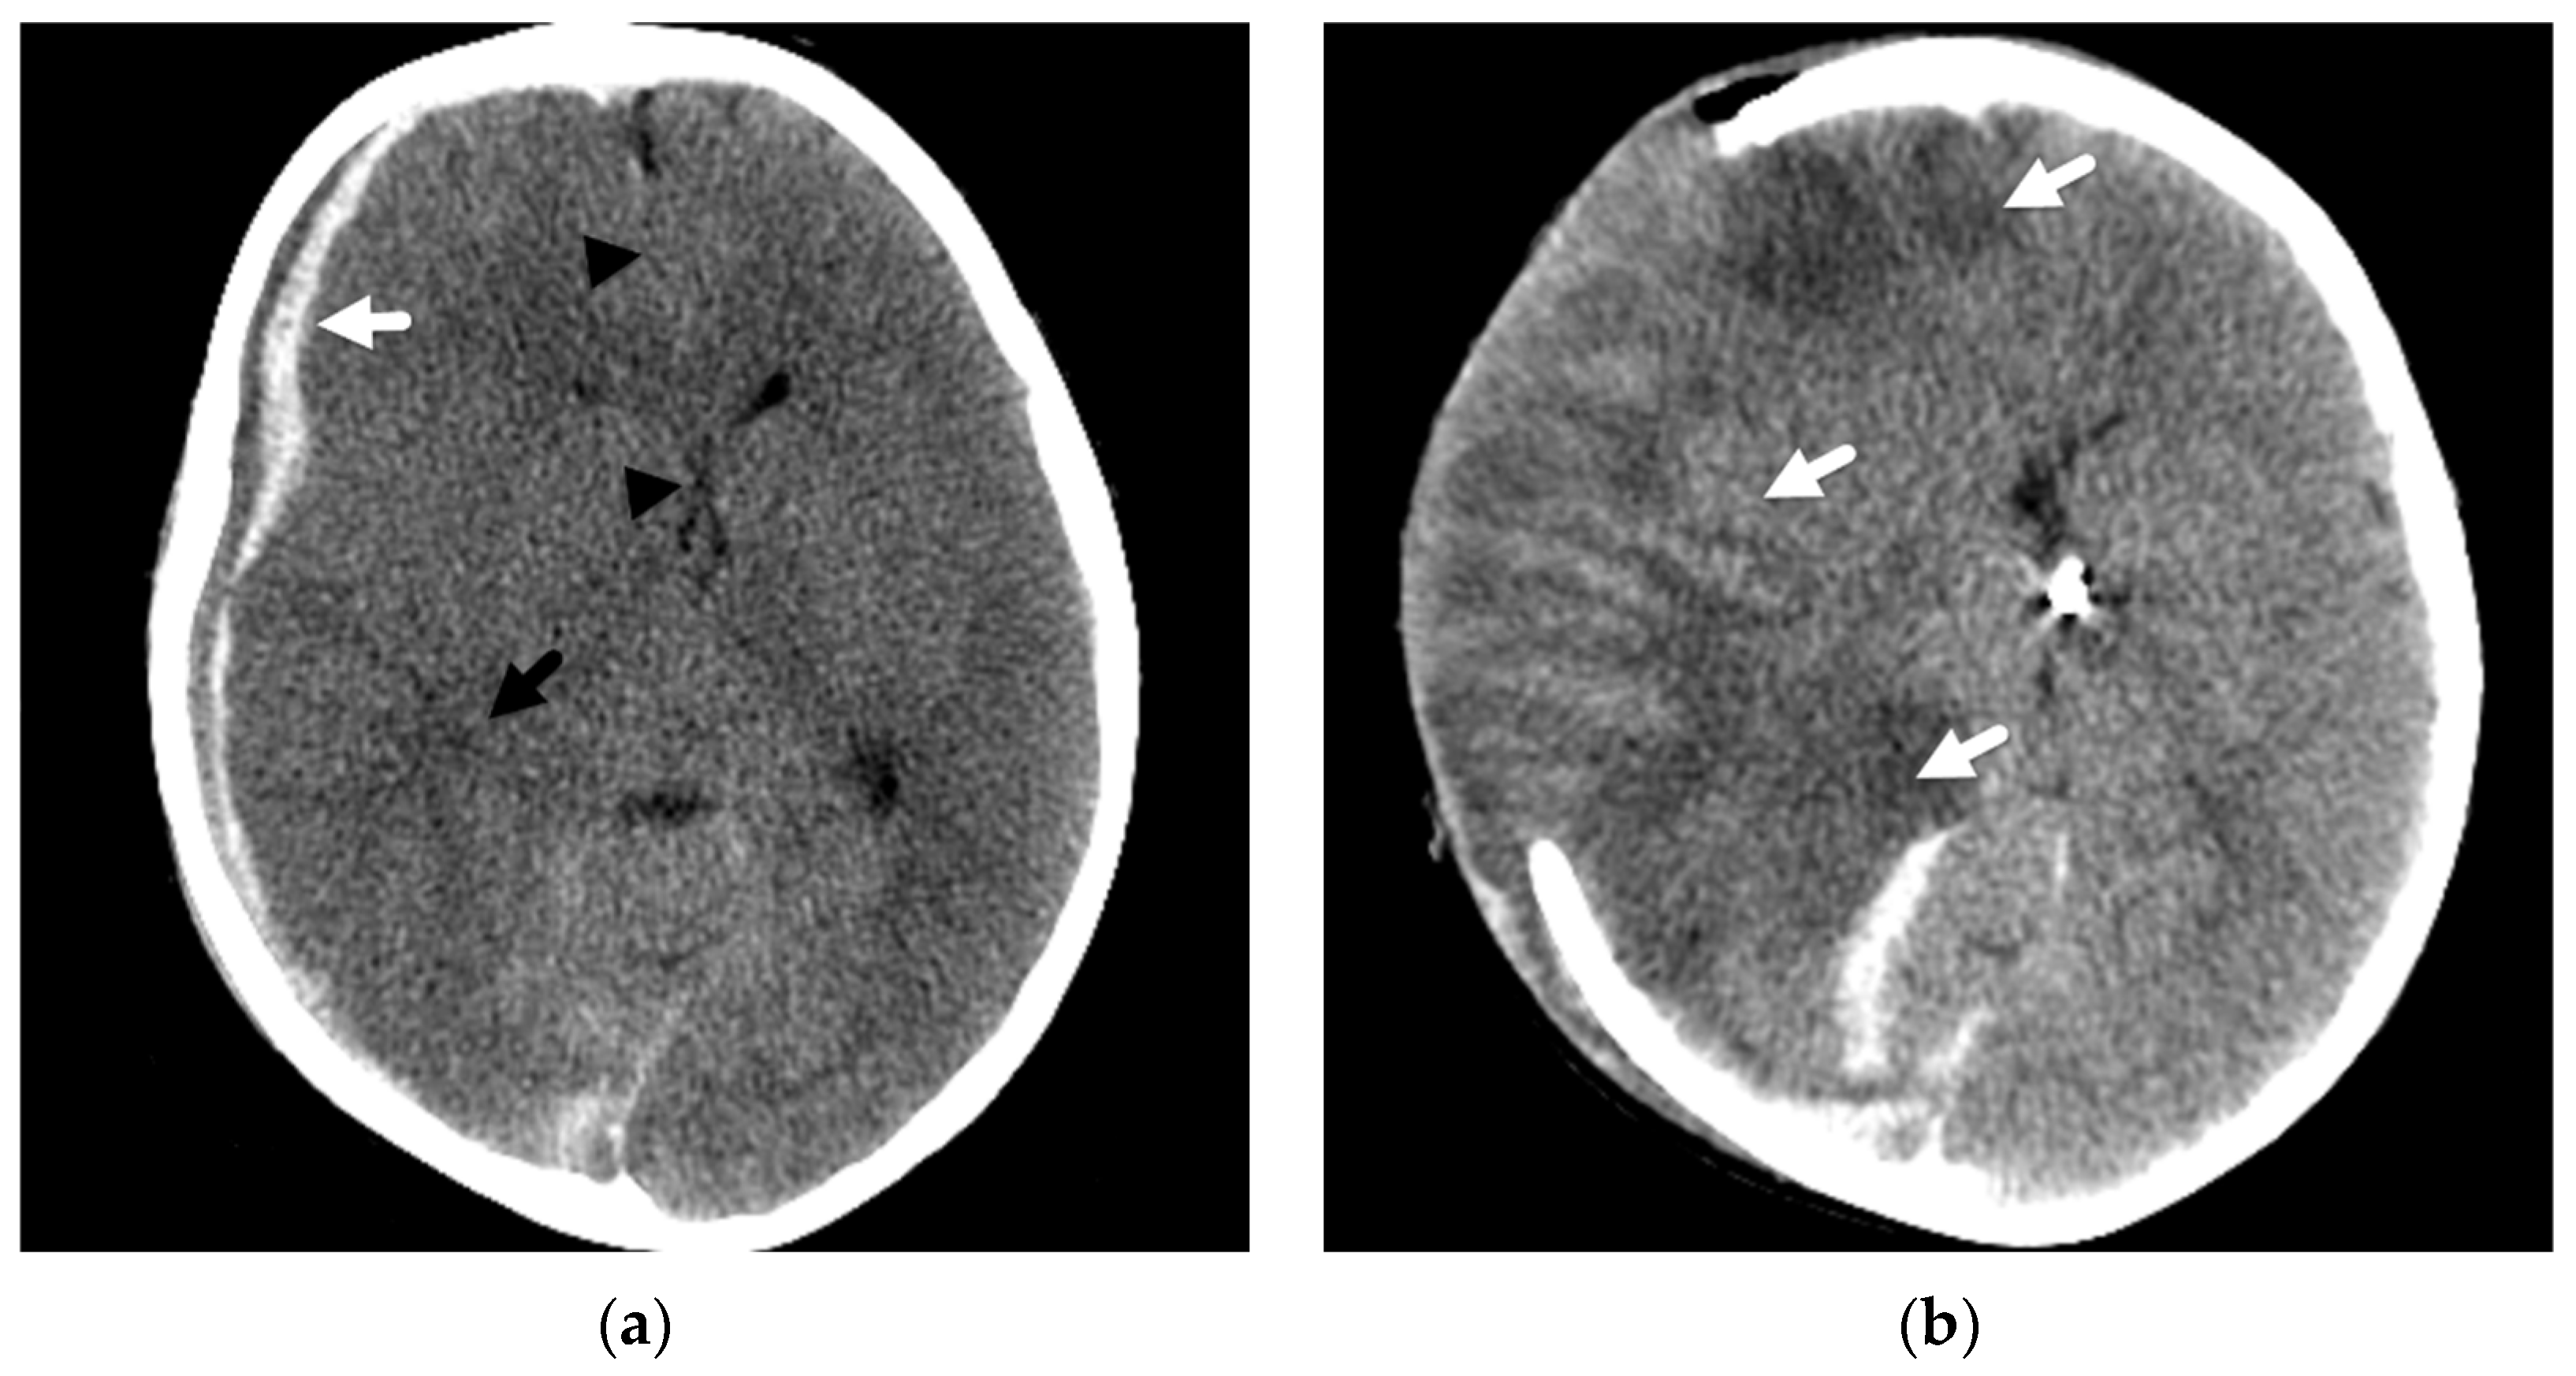

In another abusive head injury study, Foster et al. [23] described that when this unilateral pattern of hemispheric involvement was observed, coexistent subdural hemorrhage was located either bilateral or ipsilateral to the parenchymal insult but not solely contralateral in distribution [23], and the associated mass effect was often out of proportion to the volume of subdural hemorrhage (Figure 3). Some authors [40,41] have suggested that this constellation of predominantly unilateral parenchymal insult with associated SDH has similarities to a rare entity described in young athletes suffering repetitive trauma/concussions and might result from cerebral dysautoregulation. However, this remains uncertain and controversial [42], especially in reference to this younger pediatric population. As with cases presenting with a large volume subdural hemorrhage resulting in significant mass effect, these patients may undergo a decompressive hemicraniectomy in an attempt to relieve mass effect and midline shift, thus potentially alleviating subsequent infarction to areas of the contralateral brain that are more typical of herniation effects.

Figure 3.

Mixed attenuation right subdural hemorrhage in a 3-year-old female fatality presenting with abrupt mental status change and multifocal bruises after a reported fall. (a) Initial axial noncontrast head CT demonstrates a mixed attenuation subdural hemorrhage (white arrow) with mass effect, midline shift (black arrowhead), and effaced right temporal horn (black arrow); (b) next-day CT image shows changes of a decompressive hemicraniectomy with diffuse, abnormal attenuation of the right cerebral hemisphere (white arrow), which herniates through the cranial defect.